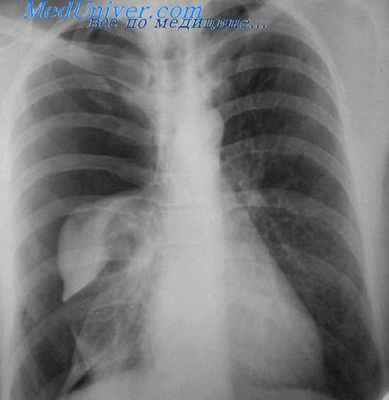

Компьютерная томография (КТ) и магнитно-резонансная томография (МРТ) — наиболее важные диагностические исследования при инсульте. КТ в большинстве случаев позволяет чётко отдифференцировать «свежее» кровоизлияние в мозг от других типов инсультов, МРТ предпочтительнее для выявления участков ишемии, оценки распространённости ишемического повреждения (это особенно важно в первые 12—24 часа заболевания, когда методом КТ ишемический инсульт может не визуализироваться). При недоступности КТ или МРТ необходимо выполнить эхоэнцефалографию и люмбальную пункцию.

Диагностические мероприятия при этой патологии сводятся к проведению компьютерной томографии, которая позволяет выявить очаг, определить его характер, размеры и локализацию. При наличии субарахноидального кровоизлияния или диагностических трудностях возможно проведение люмбальной пункции в диагностических целях.